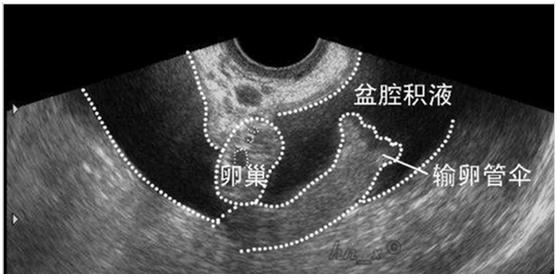

2、异位妊娠,多有不规则阴道出血、下腹痛、月经推迟等症状,尿妊娠试验阳性。

受精卵在子宫体腔以外着床的现象称为异位妊娠,最常见的是输卵管妊娠。当输卵管妊娠流产或破裂,就会输卵管壁破裂出血,血液聚积在子宫直肠陷凹,进而形成盆腔积液。从后穹窿可以抽吸出不凝固血液。